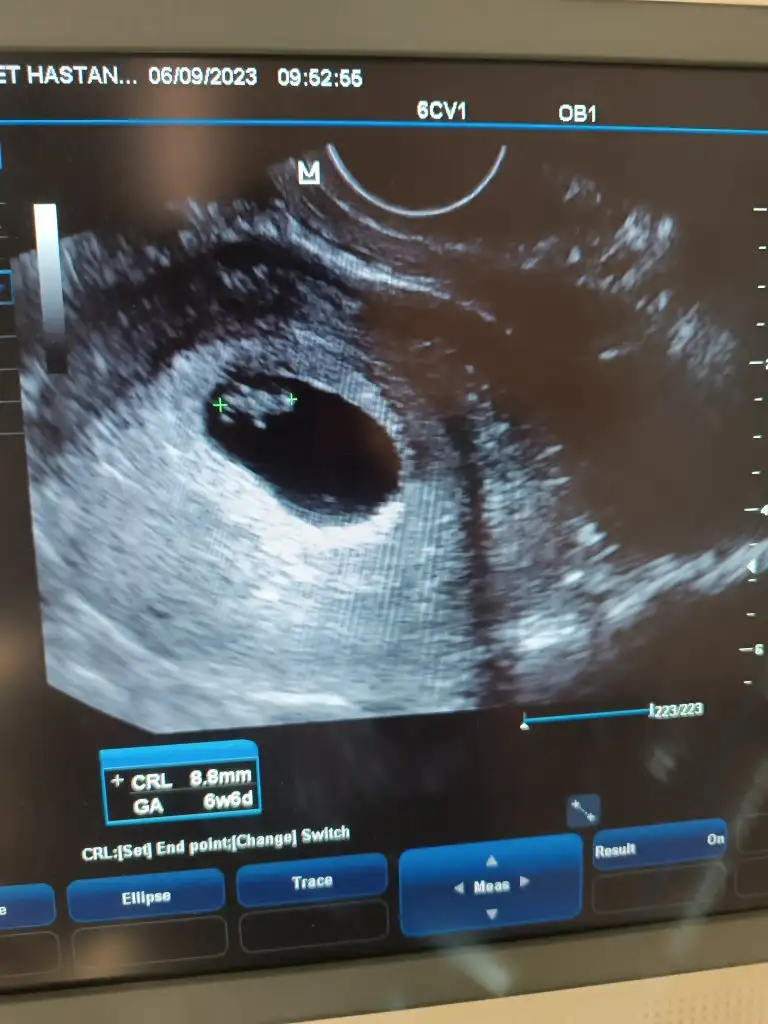

Merhabalar, 7+2 vajinal bakıldı. tahminleriniz nedir? :KK200::anneadayı: